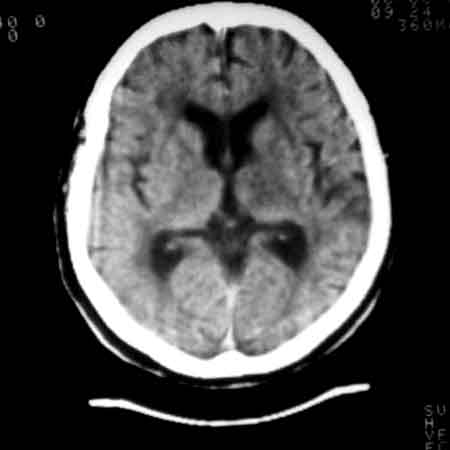

标题: CT8860:陈旧性脑出血 [打印本页]

标题: CT8860:陈旧性脑出血

女81岁,头晕、流延。

考虑:1、左丘脑区脑出血吸收期改变。

2、皮层下动脉硬化性脑病伴脑萎缩。

:1、左丘脑区脑出血吸收期改变。

2、皮层下动脉硬化性脑病伴脑萎缩

1 皮层下动脉硬化性脑病伴脑萎缩(无争议)

2 左丘脑区脑出血吸收期改变(有争议),一年出血已吸收,应为软化,边缘环形壁可能是胶质增生所致。